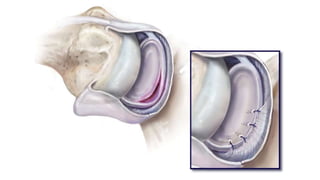

[ glenoid labrum (lip) covers excess part of the head ]- fibrocartilaginous rim

Labrum Increases humeral contact to 75%

Bankart lesion

• In I.GHL (ANTERIOR BAND)

• Mc lesion of anterior shoulder instability following anterior shoulder

dislocation.

• It involves avulsion of anterior inferior labrum

• Typically located at 3-6’ o clock position (IGHL , ANTERIOR BAND LOCATES),

where the humeral head dislocates.

• Lesion can be bony / fibrous.